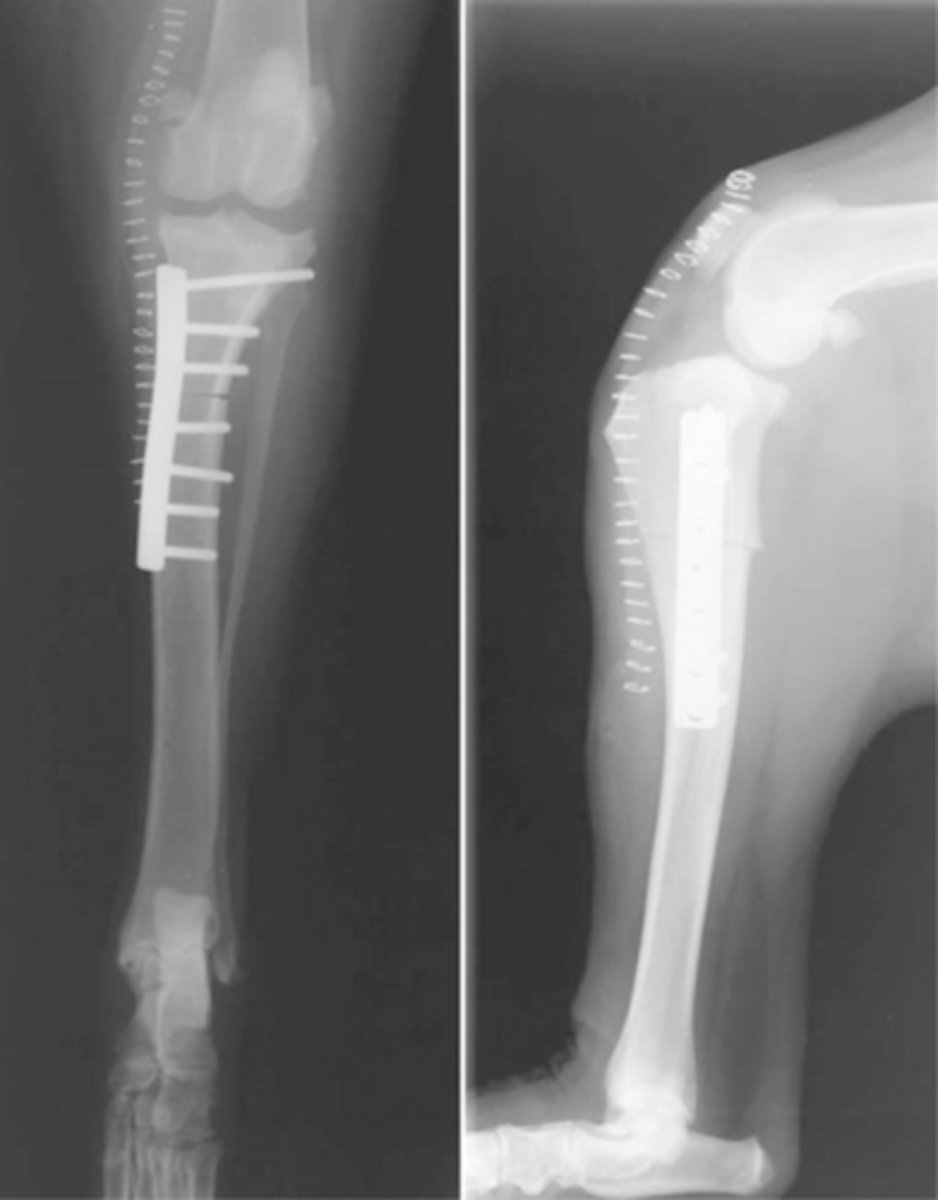

RADS for a (TWO) tibial wedge osteotomy dog

what is shown here